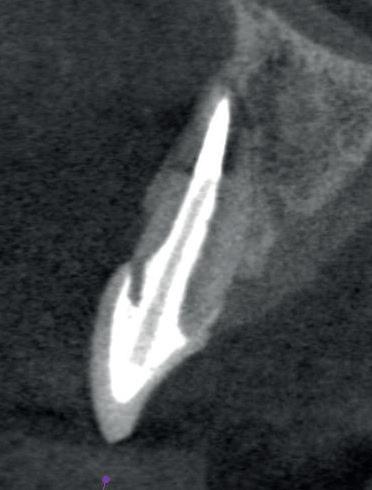

Een 47-jarige collega presenteert zich in onze verwijspraktijk voor endodontie. Hij heeft enige tijd geleden zijn kroon op de 11 laten vervangen (afbeelding 1). Omdat er geen klinische en röntgenologische aanwijzingen waren voor een periapicale laesie of een insufficiënte wortelkanaalbehandeling van de 11, werd besloten de endo, die dateerde van meer dan 30 jaar geleden, niet te reviseren (afbeelding 2). Tijdens een routinematige gebitsreiniging constateert zijn mondhygiënist een pocket van 7 mm aan de mesiopalatinale zijde van 11 (afbeelding 3). De nieuwe kroon wordt tijdelijk gecementeerd, en omdat

2: Röntgenfoto van 11 met zilverstift sectie

Er wordt een CBCT gemaakt die een laesie aan de mesiopalatinale zijde van 11 laat zien (afbeelding 4).

Na het verwijderen van de opbouw blijken er geen tekenen te zijn die op een crack of fractuur duiden, en dus gaan we verder met het verwijderen van de

5: Hedström vijl is ingebracht naast zilverstift sectie